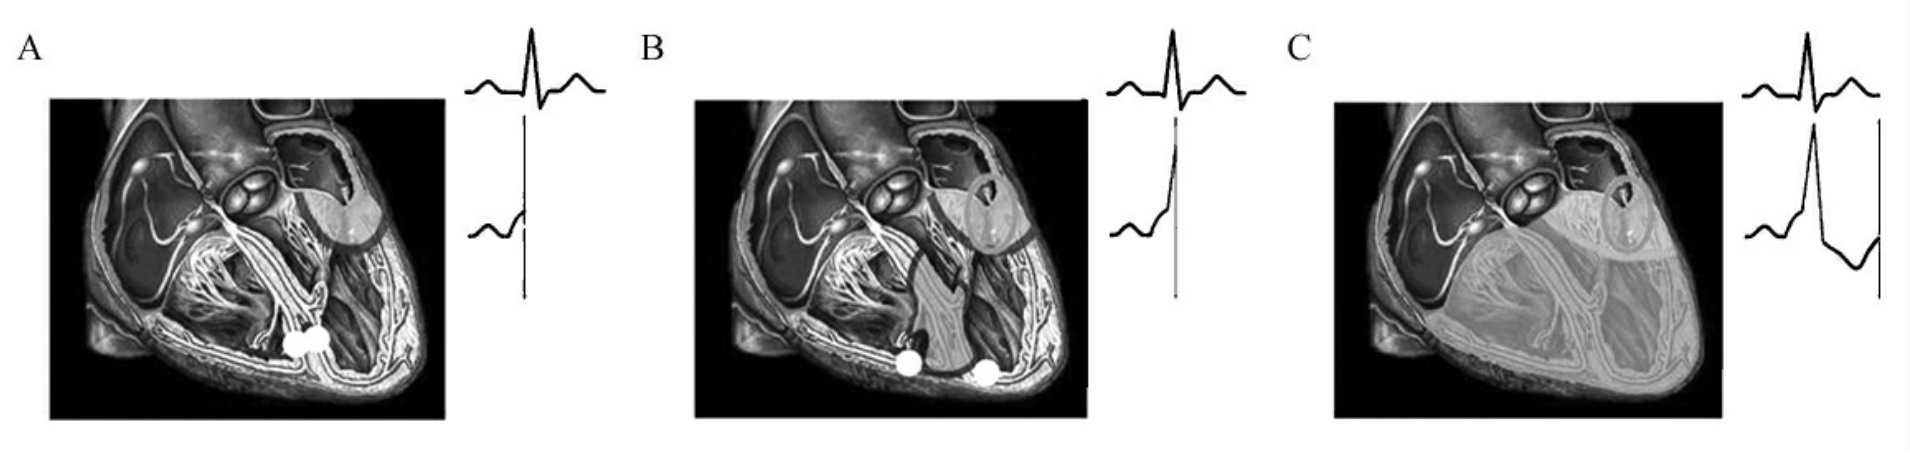

图60-190 显性预激综合征机制示意图

A.旁路预激心室形成δ波;B.正路下传心室开始快速除极δ波结束(旁路继续预激心室被掩盖);C.旁、正两路共同除极心室结束形成单源性心室融合波(在形成δ波的同时影响波形和终末向量)